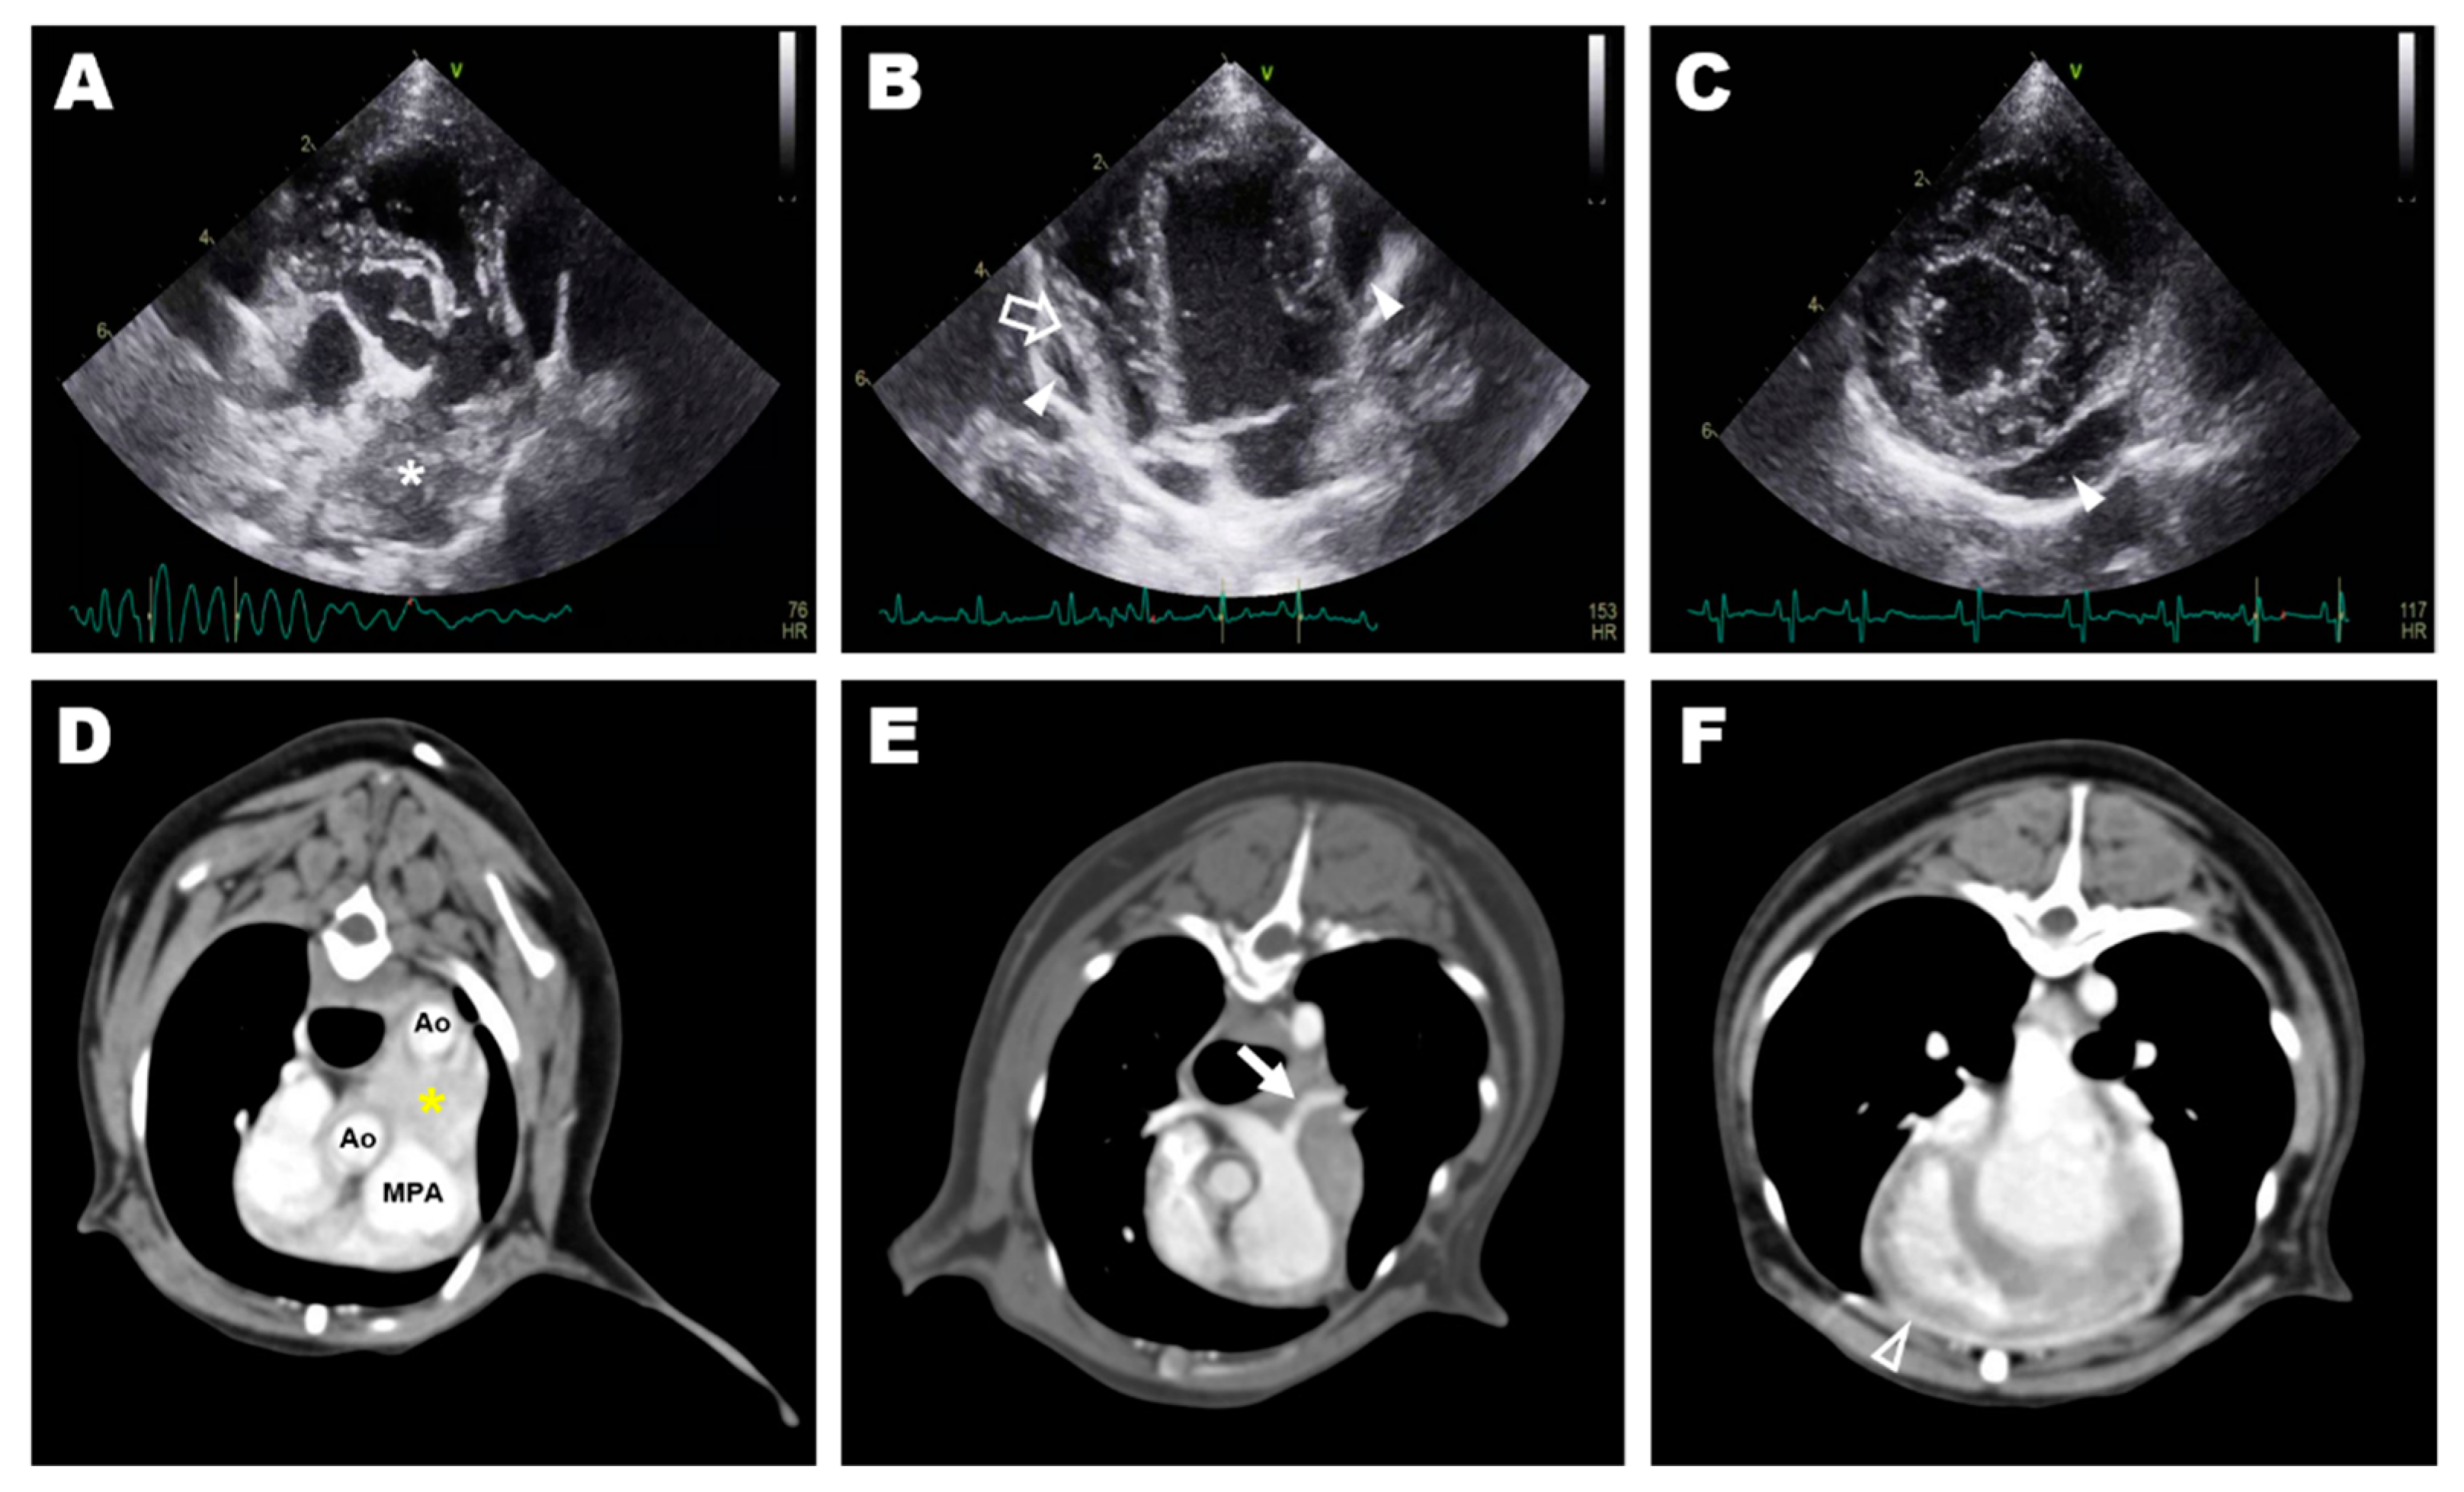

Thoracic radiography revealed cardiomegaly (VHS, 12.0v) and a bulging MPA region. An irregular and double-layered cardiac silhouette at the 3–10 o’clock position of the heart was identified in the ventrodorsal view. Transthoracic echocardiography revealed a 25 × 14 mm hypoechoic mass at the bifurcation of the MPA between the descending aorta and the MPA (Figure 1A). The left and right ventricles and the left pulmonary artery (LPA) were compressed and deviated by the mass (Figure 1B). The peak systolic velocity of the MPA at the pulmonic valve level was approximately 0.9 m/s, which was in the normal range (range; 0.81–1.18 m/s), while the peak velocity of the turbulent flow in the LPA was as high as 2.7 m/s. Additionally, a small amount of pericardial effusion was observed around the heart (Figure 1C). Mild mitral regurgitation was observed. The E wave, A wave and E/A ratio were measured as 67 cm/s, 49 cm/s, and 1.37, respectively. Peak aortic valve velocity (AV Vmax) was 1.4 m/s, and the left ventricular outflow tract velocity time integral (LVOT VTI) was 9.3 cm. Fractional shortening (FS) was 22.39%. Residual shunt flow was not observed. A heterogeneous lesion in the anterior heart base between the aorta and the MPA (Figure 1D), including a 20 × 15 × 10 mm hypodense mass without contrast enhancement, was identified on computed tomography (CT). The LPA was narrowed compared to the right pulmonary artery due to compression by the heart base mass (Figure 1E). The thickness of the pericardium before contrast was approximately 2 mm with soft tissue density, and contrast enhancement was confirmed for the thickened pericardium after an injection of contrast media (Figure 1F). Granuloma formed by the suture material, granulomatous inflammation, heart base tumor, pericardial effusion, pericarditis, and pericardial abscess were considered in the differential diagnosis for the periaortic mass. The clinical signs were presumed to be caused by the mass and inflammation around the heart, and exploratory thoracotomy and pericardiectomy were performed to relieve the clinical symptoms and obtain biopsy specimens of the mass.

Figure 1. Preoperative diagnostic imaging: transthoracic echocardiography (AC) and transverse image of computed tomography (DF); (A) hyperechoic mass (asterisk) at the bifurcation of the main pulmonary artery identified at aortic root level short-axis view of the right parasternal window; (B) pericardial effusion (arrowhead) and deviated free wall of the right ventricle (blanked arrow) identified at the apical four-chamber view of the left parasternal window; (C) small amount pericardial effusion (arrowhead) identified at the short-axis view of the right parasternal window; (D) a heterogeneous lesion (yellow asterisk) in the anterior heart base between the aorta and the main pulmonary artery; (E) stenosed left pulmonary artery (arrow) caused by compression of the heart base mass; (F) thickened pericardium with post-contrast enhancement (blanked arrowhead).